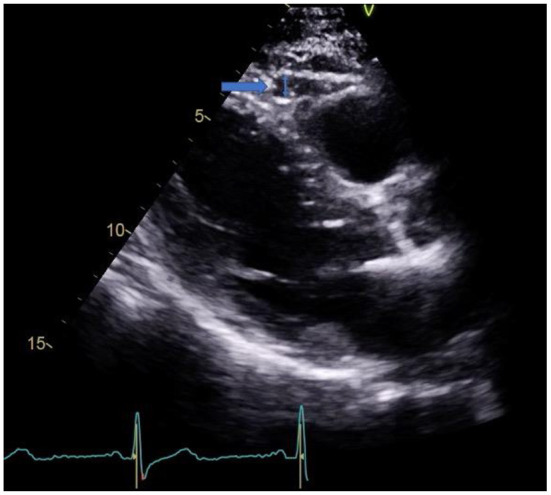

Single-center, observational, prospective cohort of 41 patients with a first episode of AMI treated with percutaneous coronary revascularization. All patients were admitted to the hospital as part of the protocol “Infarction Code” for primary percutaneous coronary intervention (PPCI). All patients underwent transthoracic echocardiography (TTE) within the first 24–48 h after hospital admission. The thickness of EAT was quantified in an end-diastole parasternal long-axis image at the level of the right ventricular free wall, Figure 1. 2D conventional parameters were obtained, as well as speckle tracking derived parameters, such as global longitudinal strain (GLS). CMR was performed 5–7 days after MI diagnosis with a 1.5 Tesla system and included steady-state free precession sequences (SSFP), and T1-weighted sequences for late gadolinium enhancement (LGE). LGE quantification was done by the semi-automated fullwidth at half-maximum (FWHM), defining infarct as myocardium with signal intensity (SI) > 50% of the peak SI in the infarct core. Microvascular obstruction (MVO) was defined as a hypo-enhanced region within the infracted myocardium in post-contrast images. T1 time quantification was obtained through Modified Look-Locker Inversion Recovery (MOLLI) sequences before and 15 min after the administration of gadolinium (0.2 mmol/kg). For myocardial extracellular volume (ECV), a region of interest (ROI) was placed in the LV myocardium to acquire pre- and post-contrast myocardial T1 values. At the level of the LV blood pool, another ROI was placed to assess the pre- and post-contrast blood T1 values. ECV was calculated with the following formula: ECV = (1 – hematocrit) Å~ (Δ R1 myocardium/Δ R1 blood). All images were analyzed with the software Medis Suite, version 3.2 (Medis Medical Imaging Systems. Leiden, The Netherlands).

Figure 1.

EAT in parasternal long axis view.